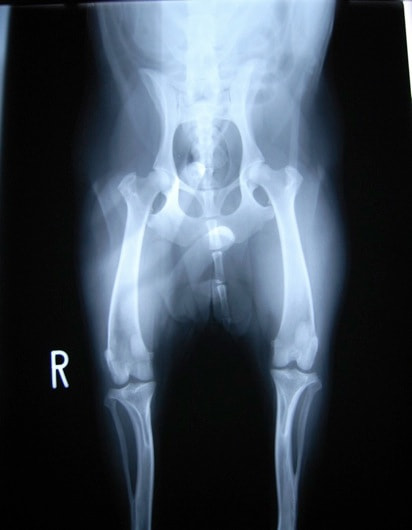

■ 症例24 キャバリア 7か月

左右膝蓋骨内方脱臼(左:グレードⅣ 右:グレードⅢ)

以前から左右後肢の跛行が認められ、整形外科学的検査・レントゲン検査により左右の膝蓋骨脱臼が認められた。症状が重度である左膝の膝蓋骨脱臼整復術を行った。外科手技は縫工筋及び内側広筋の解放、脛骨粗面の外側転位、滑車ブロック形造溝術、内外側関節方の縫縮を実施した。術後一か月時点で、左の膝蓋骨は安定しており経過は良好である。

本症例は成長期における重度の膝蓋骨脱臼であり、術後の再発の可能性もあるため、経過をしっかりと観察していく必要がある。また、今回手術を実施していない右膝に関しても経過を観察し、手術を検討していくこととする。